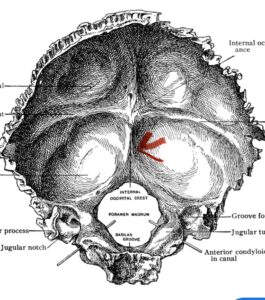

Fig. 1: Diagram of occipital bone to foramen magnum. Note external occipital protuberance (red arrow)

Although some patients do not require a decompression and just require an occipital cervical fusion, most require some sort of decompression of the neural elements. After a decompression an instrumented fusion is performed. A useful anatomic structure for anchoring the top portion of the construct to the skull is the midline keel of the subocciput. This structure extends from the external occipital protuberance, which corresponds to the confluence of the sagittal and transverse sinuses, to just above the foramen magnum:

(Fig. 1). This bone is quite thick, about 15 mm (Figs. 2a and b). Most modern plate systems utilize three midline keel screws with the option to place within a 2 cm lateral fixation point. This plate is connected to sometimes tricky-to-bend rods and connected to screw fixation points in the cervical spine (Fig. 3). Bone graft material extends from skull to cervical spine.